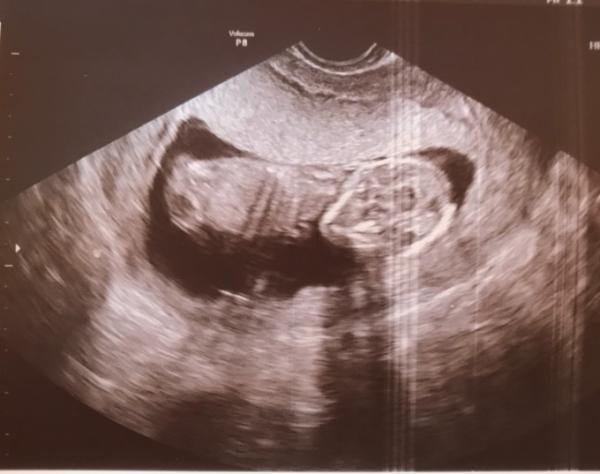

Hallo ihr Lieben Ich war heute nach 4 langen Wochen endlich wieder beim Frauenarzt! Zum Glück geht es dem Baby gut und es ist alles zeitgerecht entwickelt Da ich beim letzten Mal im Bereich des Muttermunds eine Flüssigkeitsansammlung hatte, hat er auch einen Ultraschall gemacht und die Flüssigkeit war zum Glück fast komplett verschwunden und mein Baby durfte ich dann auch gleich noch bewundern es hat sich richtig schön bewegt und mit dem ganzen Körper herumgezappelt, das war so schön zu sehen! Zum Geschlecht hat der FA leider noch nix gesagt und leider habe ich den nächsten Termin jetzt erst in 6 (!!) Wochen! Keine Ahnung wie ich das aushalten soll... Wie geht’s euch so? Liebe Grüße

Wow ein tolles Foto! Ja 6 Wochen sind wirklich lange , es ist unerträglich die Warterei... jedesmal wieder egal die wievielte so es ist... Ich habe am 18.12 Termin und zähle schon die tage